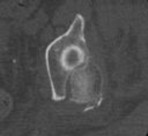

A 22-year-old rugby player has a history of recurrent anterior shoulder instability. A 3D reconstructed pre-operative CT scan is shown. The imaging demonstrates an inverted pear-shaped glenoid with a calculated anterior-inferior bone loss of 27%. What is the most appropriate surgical management to minimize his recurrence risk?

Options:

- Arthroscopic Bankart repair with capsular plication

- Arthroscopic remplissage alone

- Open inferior capsular shift

- Latarjet procedure (coracoid transfer)

- Thermal capsulorrhaphy

Correct Answer: Latarjet procedure (coracoid transfer)

Explanation:

In patients with anterior shoulder instability and significant glenoid bone loss (>20-25%, often creating an 'inverted pear' appearance), soft tissue procedures alone (like an arthroscopic Bankart repair) have unacceptably high recurrence rates. A bony augmentation procedure, most commonly the Latarjet procedure (transfer of the coracoid process with the attached conjoint tendon to the anterior glenoid neck), is the gold standard treatment.